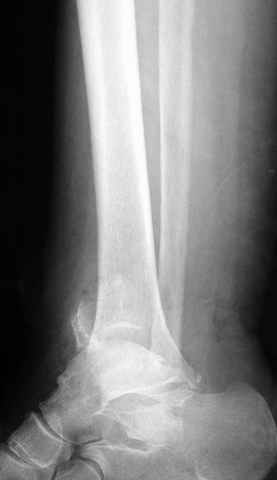

Второй случай сделан из одного разреза

ЕЧ LISS plate, mininvasive approach - luxurous !

На прямой проекции послеоперационного Рг макроскопически все выглядит очень анатомично, при микроскопическом ( :-)) ) рассмотрении можно все-таки заметить вальгизацию тарана, суставная щель в латеральном отделе сустава несколько уже , чем в медиальном при отсутствии латерального смещения тарана. У меня был аналогичный случай (без LISS , без мини доступа) с вальгусным наклоном тарана при восстановленном ankle mortise при последовательном наблюдении с интервалами в 6-8 недель в послеоперационном периоде отмечалось прогрессирующее сужение суставной щели в латеральном отделе сустава, закончившееся посттравматическим ОА, к счастью боли умеренные, купируемые аналгетиками или своими эндорфинами:-))(активная пациентка, у которой нет времени на болезни....) Какова жизненная ситуация в приведенном вами случае? И последнее, что я хотел бы прояснить для себя - фиксация внутренней лодыжки: я обычно комбинирую фиксацию компрессирующим винтом со спицей - по идее ротационная стабильность должна быть лучше, чем один винт, каковы ваши наблюдения в этом плане?